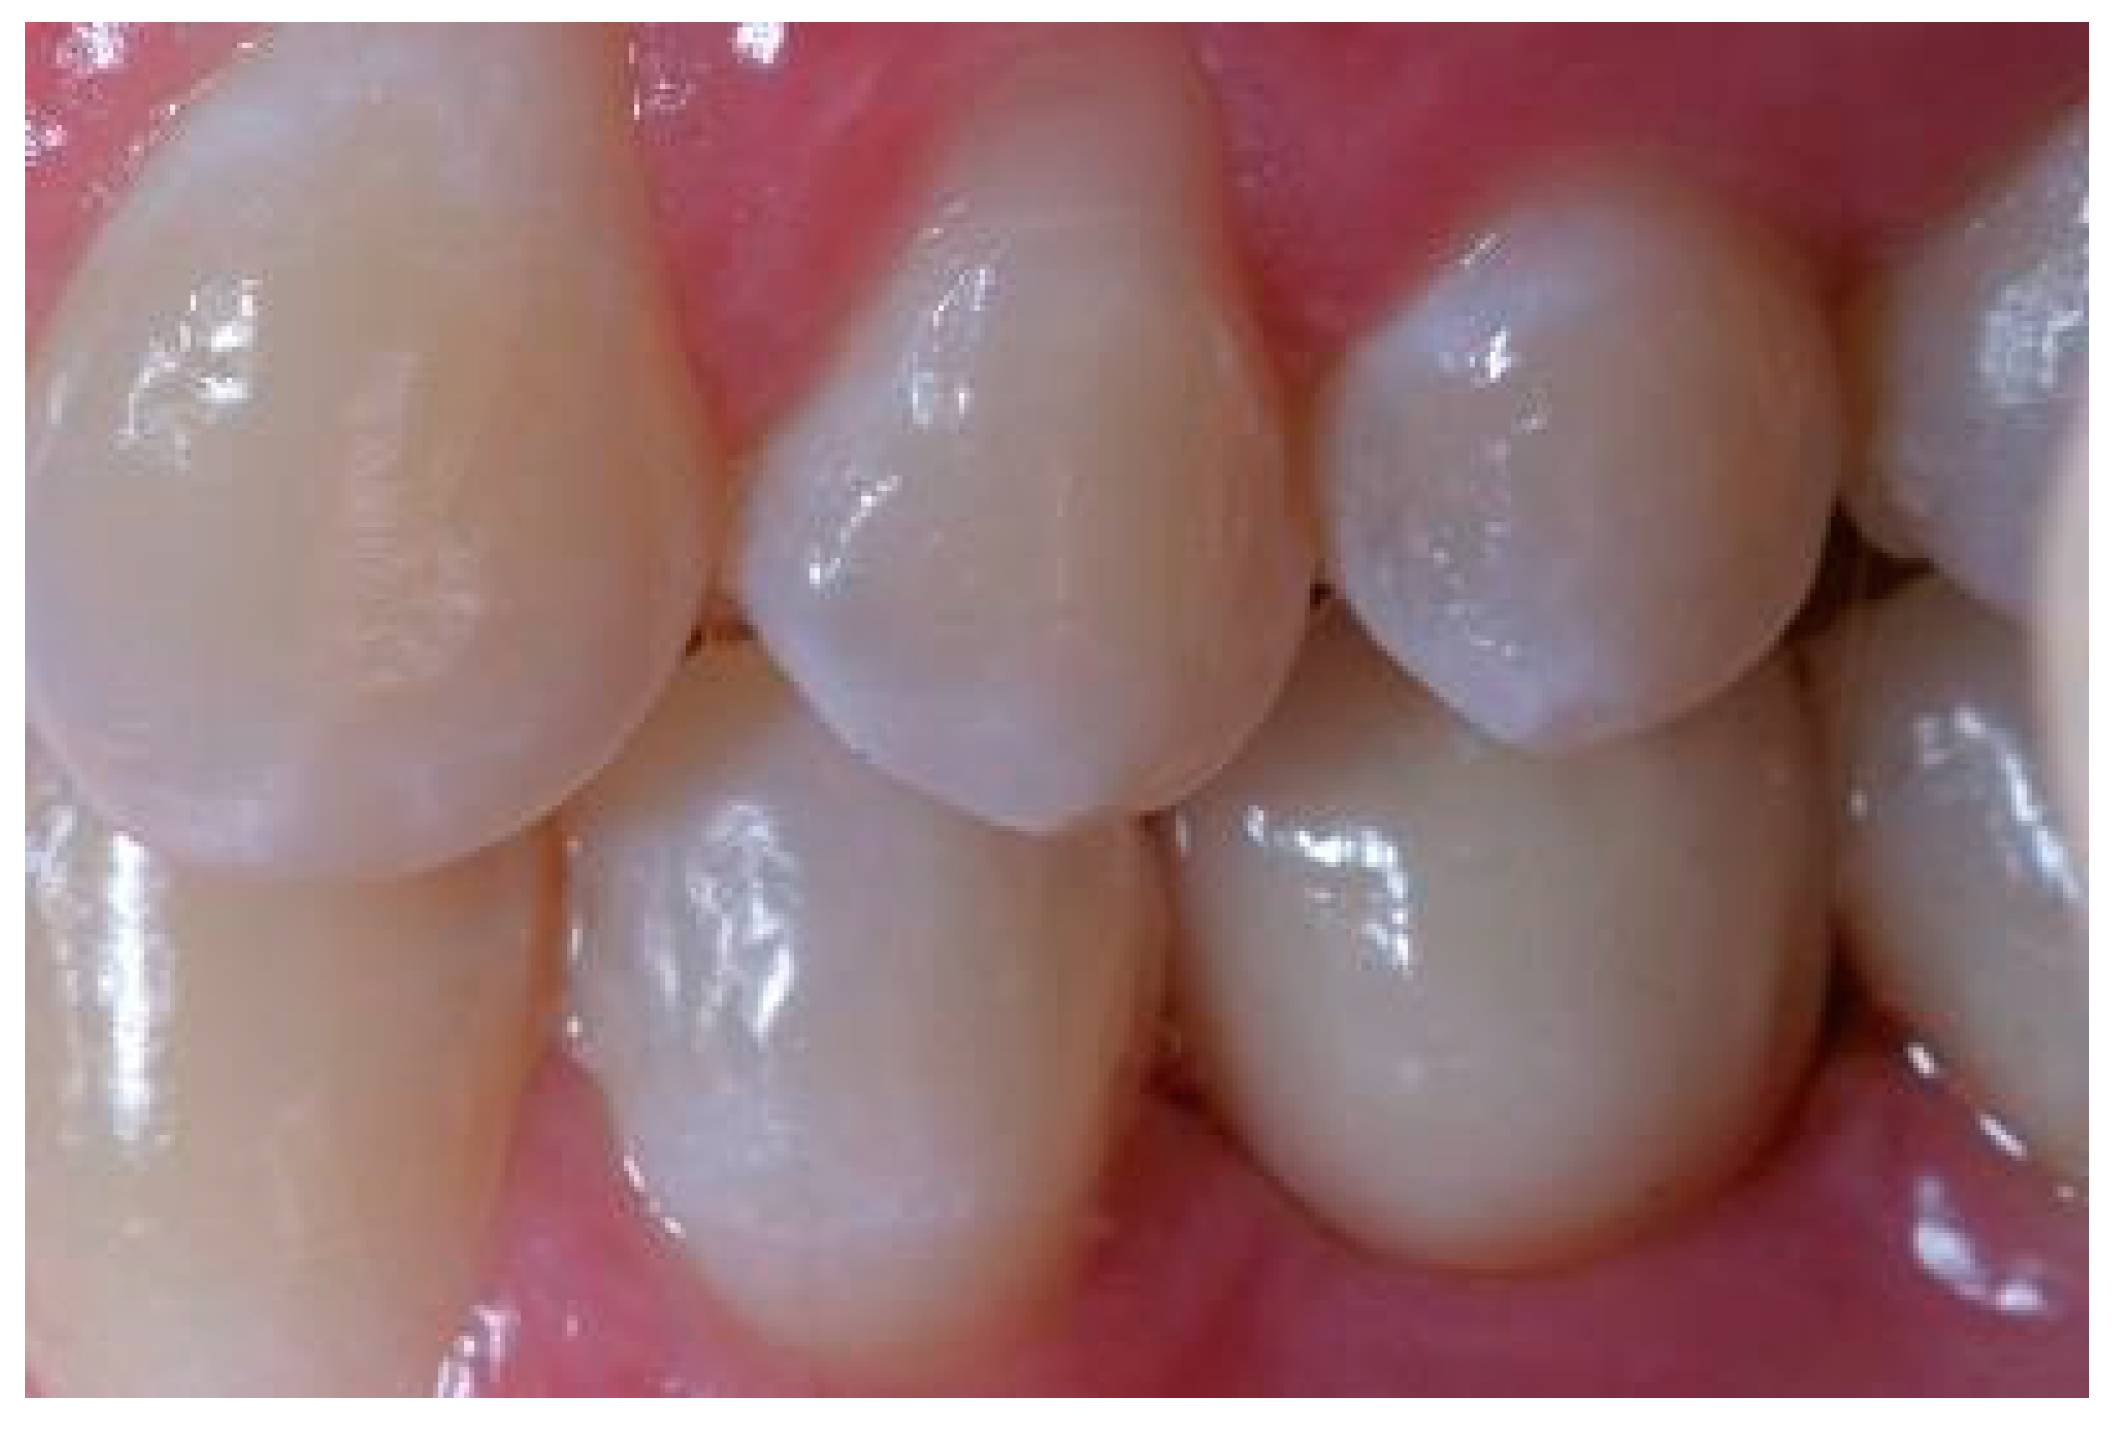

Situation after crown cementation. Lateral view.

Figure A2.

Clinical situation at the 1-year follow-up. Lateral view.

Figure A5.

Clinical situation at the 3-year follow-up. Lateral view.

Figure A8.

Clinical situation at the 5-year follow-up. Lateral view.

Figure A11.